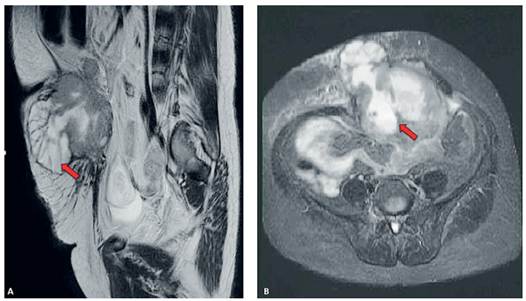

Paciente de 45 años, que consultó por cuadro de 4 meses caracterizado por síndrome constitucional, asociado a dolor abdominal difuso de poca intensidad. Al examen físico se palpó en mesogastrio una masa indurada, que generaba dolor a la manipulación. La tomografía computarizada reveló un tumor mixto a nivel del mesogastrio, que comprometía la región subfascial y el tejido celular subcutáneo, con captación del medio de contraste. En la resonancia magnética nuclear se visualizó un tumor que involucraba el tejido celular subcutáneo y la región muscular, asociado a congestión linfática (Figura 1). Se postuló la posibilidad de un sarcoma de pared abdominal, por lo cual se realizó biopsia con aguja gruesa. El reporte de patología informó un carcinoma escamocelular moderadamente diferenciado con queratinización.